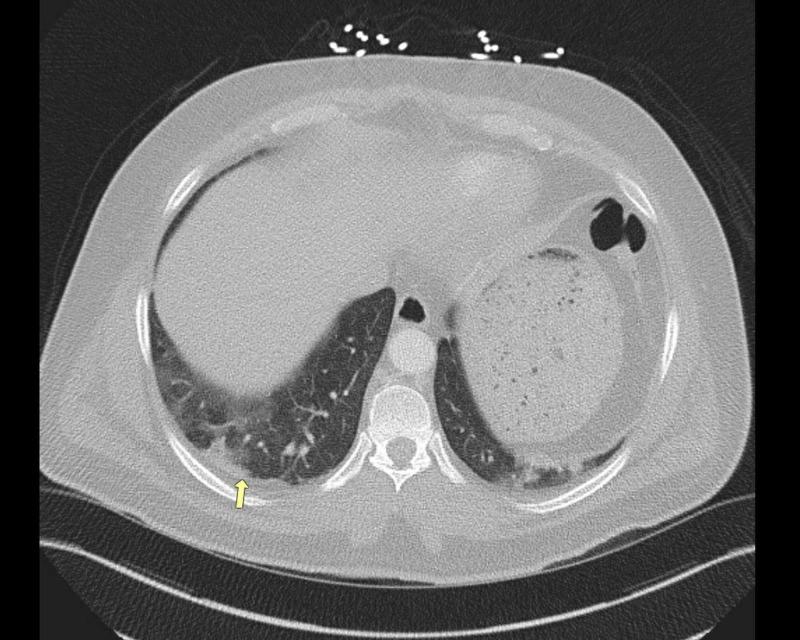

奥美拉唑起始治疗后表现为横纹肌溶解的多发性肌炎

Polymyositis Presenting as Rhabdomyolysis After the Initiation of Omeprazole.

Rhabdomyolysis is a clinical syndrome with a wide range of presentations; it results in muscle necrosis and release of intracellular muscle contents into the circulation. Inflammatory myopathies are a rare cause of rhabdomyolysis. We present a case of a 46-year-old male with a two-week history of progressively worsening diffuse muscle pain after he had been prescribed omeprazole one month prior. A creatine phosphokinase (CPK) elevation was noted, which persisted despite treatment with IV fluids, sodium bicarbonate, and close correction of electrolytes. Further workup, including autoimmune and infectious etiologies, was notable for elevated antinuclear antibodies (ANA), erythrocyte sedimentation rate (ESR), and C-reactive protein (CRP). Furthermore, a muscle biopsy showed evidence of endomysial inflammatory cells, consistent with a diagnosis of polymyositis. Steroids were initiated with significant improvement in symptoms and a decrease in CPK levels. The patient was discharged on a tapering dose of steroids and, on follow-up with the rheumatologist, transitioned to methotrexate with control of symptoms. In patients with rhabdomyolysis who do not respond to first-line therapy, obtaining a detailed medication history and screening with ANA and ESR are encouraged. Given the link between medication and autoimmune disease, clinicians should consider autoimmune myopathy in the differential for cases with persistently elevated creatine kinase. Prompt diagnosis with early initiation of immunosuppressive medication may improve outcomes and avoid complications associated with untreated rhabdomyolysis or polymyositis.

摘要